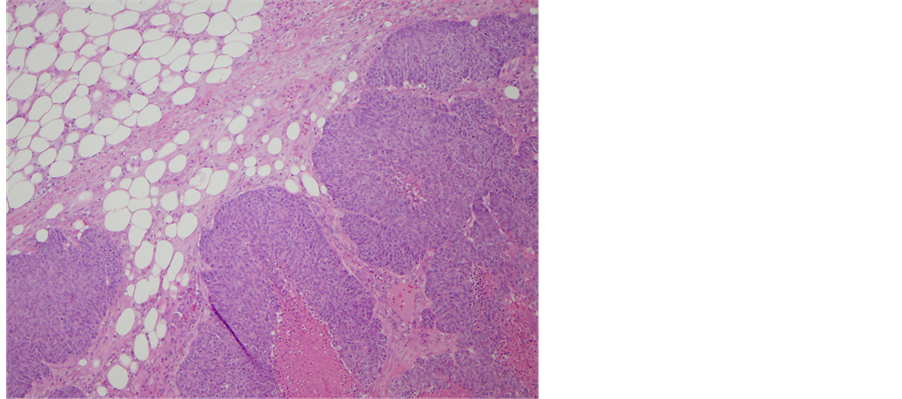

April 2014: Final pathological diagnosis of April 2014: Endometrioid adenocarcinoma, grade 2 of 3, with limited superficial myometrial invasion to 1 mm and without cervical or vascular invasion. No diagnostic abnormalities were recognized in the ovaries, fallopian tubes and omentum (Figure 2 and Figure 3).

Figure 2. Grade 2 endometrioid adenocarcinoma with superficial invasion (10× magnification).

Figure 3. Grade 2 endometrioid adenocarcinma in the uterine specimen (50× magnification).